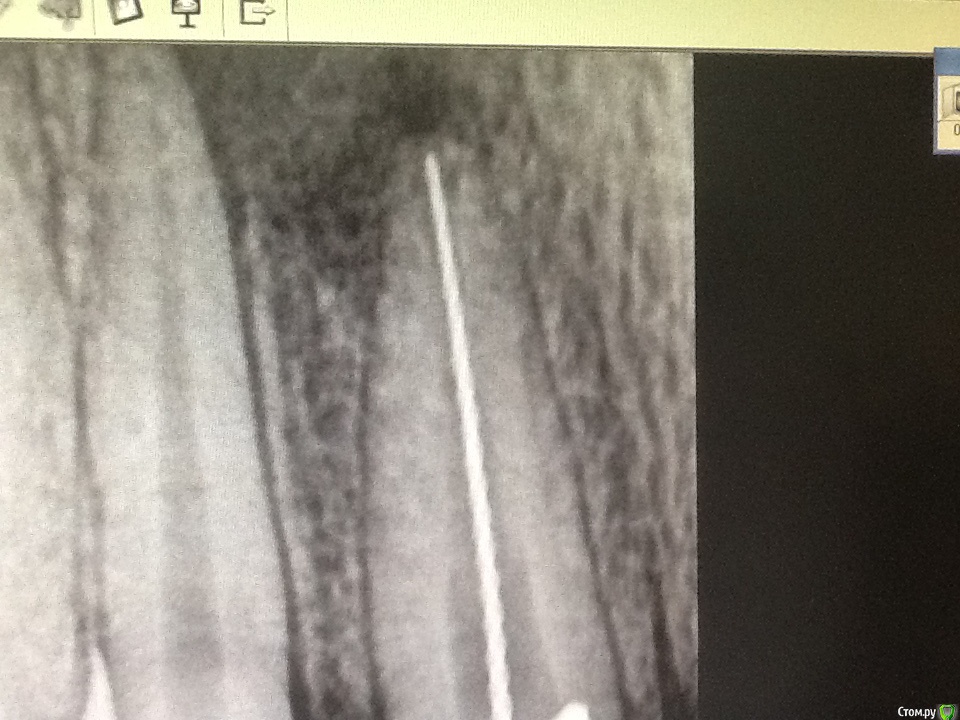

Каплан Опубликовано 8 октября, 2015 Автор Поделиться Опубликовано 8 октября, 2015 В мед каналах 3.6 происходит отложение заместит дентина. Ты уверен что воспаление там обратимо? Если потом придётся делать эндо, проблемы могут быть с прохождением каналов. Пульпа в апексе причём будет уже дохлая. Был недавно аналогичный случай у мальчика 14 лет. Травма в 6 лет возрасте, облитерация 1/3 канала, прислали на микроскоп. Я не могу сказать что было очень сложно. Но у детского стоматолога это вызвало проблемы. Могу показать снимок, если интересноДумаешь не стоит уже ждать закрытия апексов и сделать эндо? Ссылка на комментарий

Л Ю С Я Опубликовано 8 октября, 2015 Поделиться Опубликовано 8 октября, 2015 Думаешь не стоит уже ждать закрытия апексов и сделать эндо? Трудно сказать. Они и при периодонтите могут закрыться, эндо конечно же легче сделать при сформированной верхушке. Главное чтоб резорбция не началась. Я бы понаблюдала ещё год. Сколько лет ребёнку ? Ссылка на комментарий